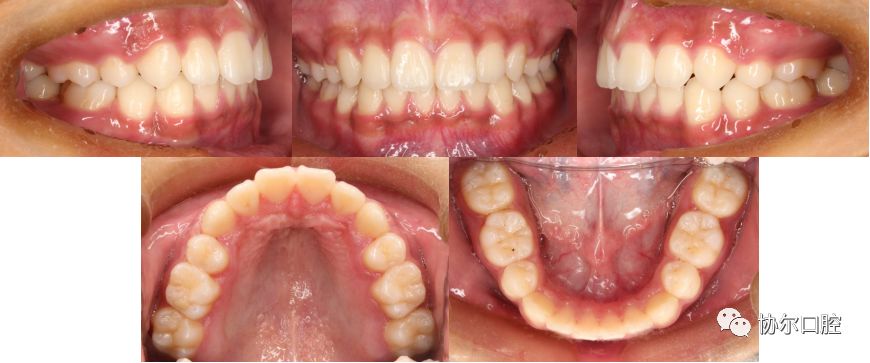

关键词:牙列拥挤;前突,深覆合深覆盖

矫治方法:拔牙矫治;固定治疗

矫治时间:22个月

治疗前口内相:

治疗后口内相